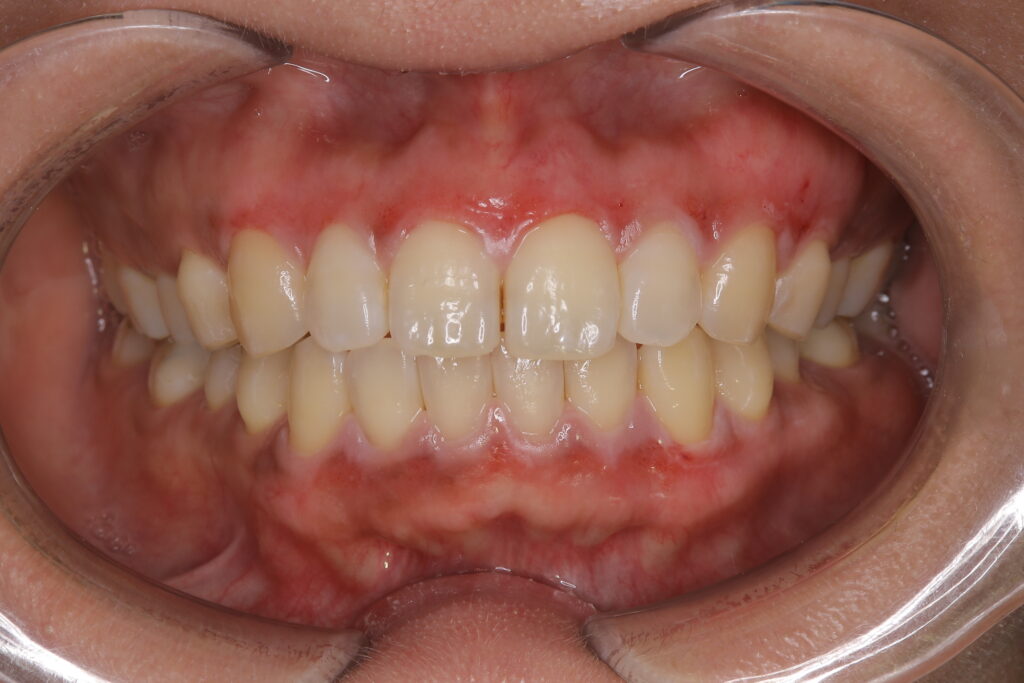

6. 術後1ヶ月

赤みも落ち着いて綺麗なピンク色になりました🌟